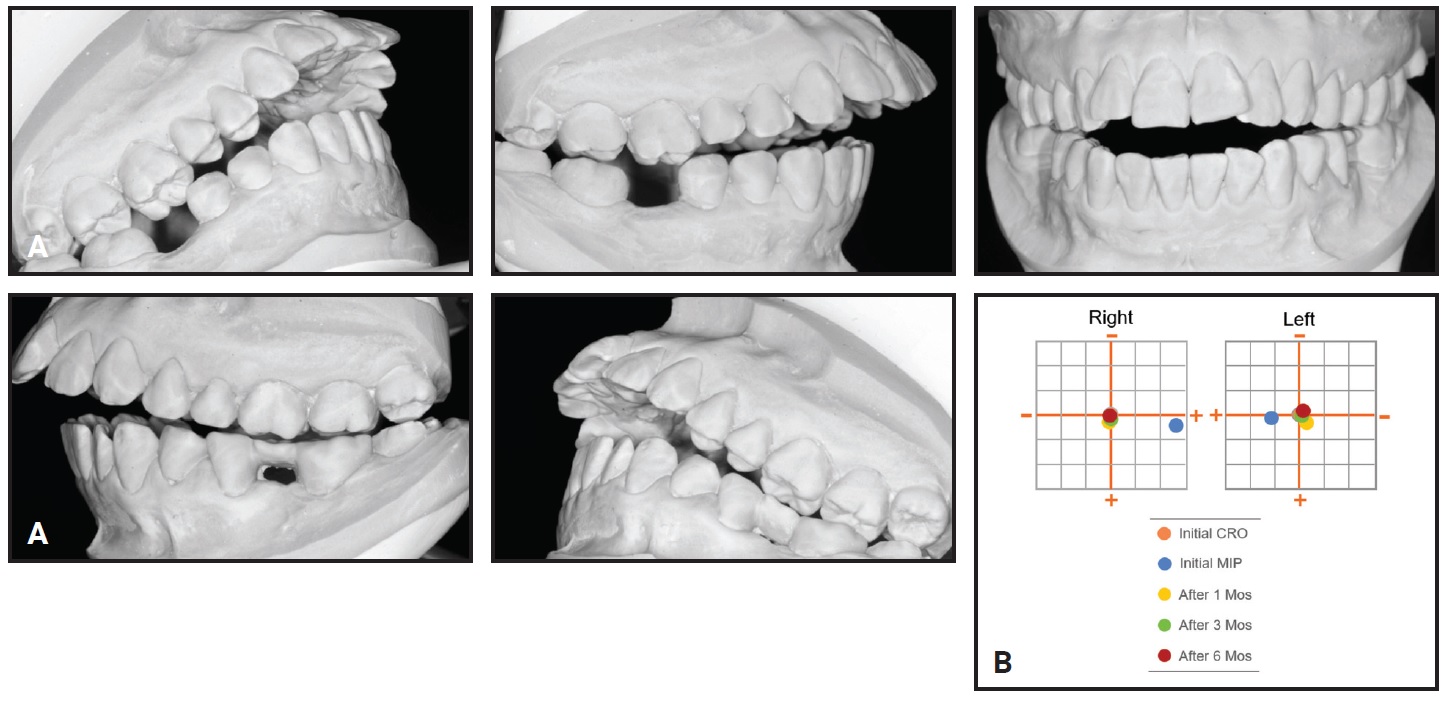

Post-treatment dental cast measurements of the WALA ridge were increased by 5mm at the mandibular canines and 2.5mm at the first premolars10 (Fig. 6).

Fig. 6 A. WALA ridge10 before treatment. B. After treatment.

This arch expansion was obtained not only by lateral tooth movement, which increased the intercanine, interpremolar, and intermolar widths, but also by alveolar bone remodeling following movement of the teeth.9